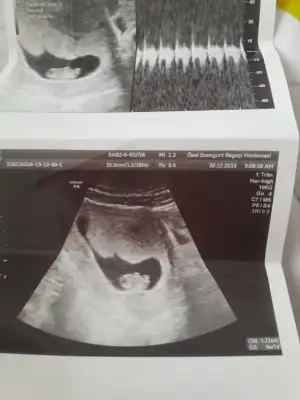

MaşAllah canımEki Görüntüle 2570165 bugün kontrolum vardı kizlar

Eki Görüntüle 2570165 bugün kontrolum vardı kizlar

Benim rahim ters vajinal baktı ve bebegide gördük ben 5+3um bugun